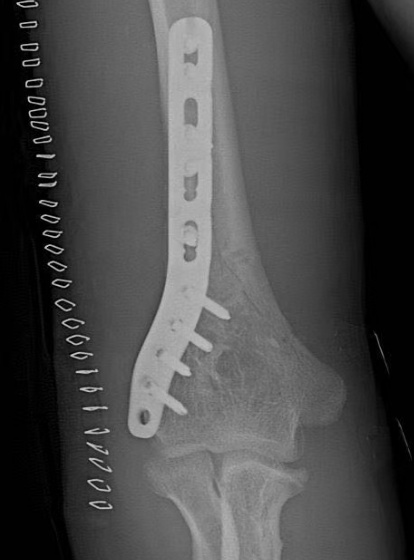

对骨折移位明显、粉碎或合并神经损伤的患者,往往需要考虑手术治疗,多复位后用钢板或髓内钉固定骨折部位。目前的研究及临床治疗来看,该类骨折的恢复情况尚好,即使有神经损伤极少留下后遗症。